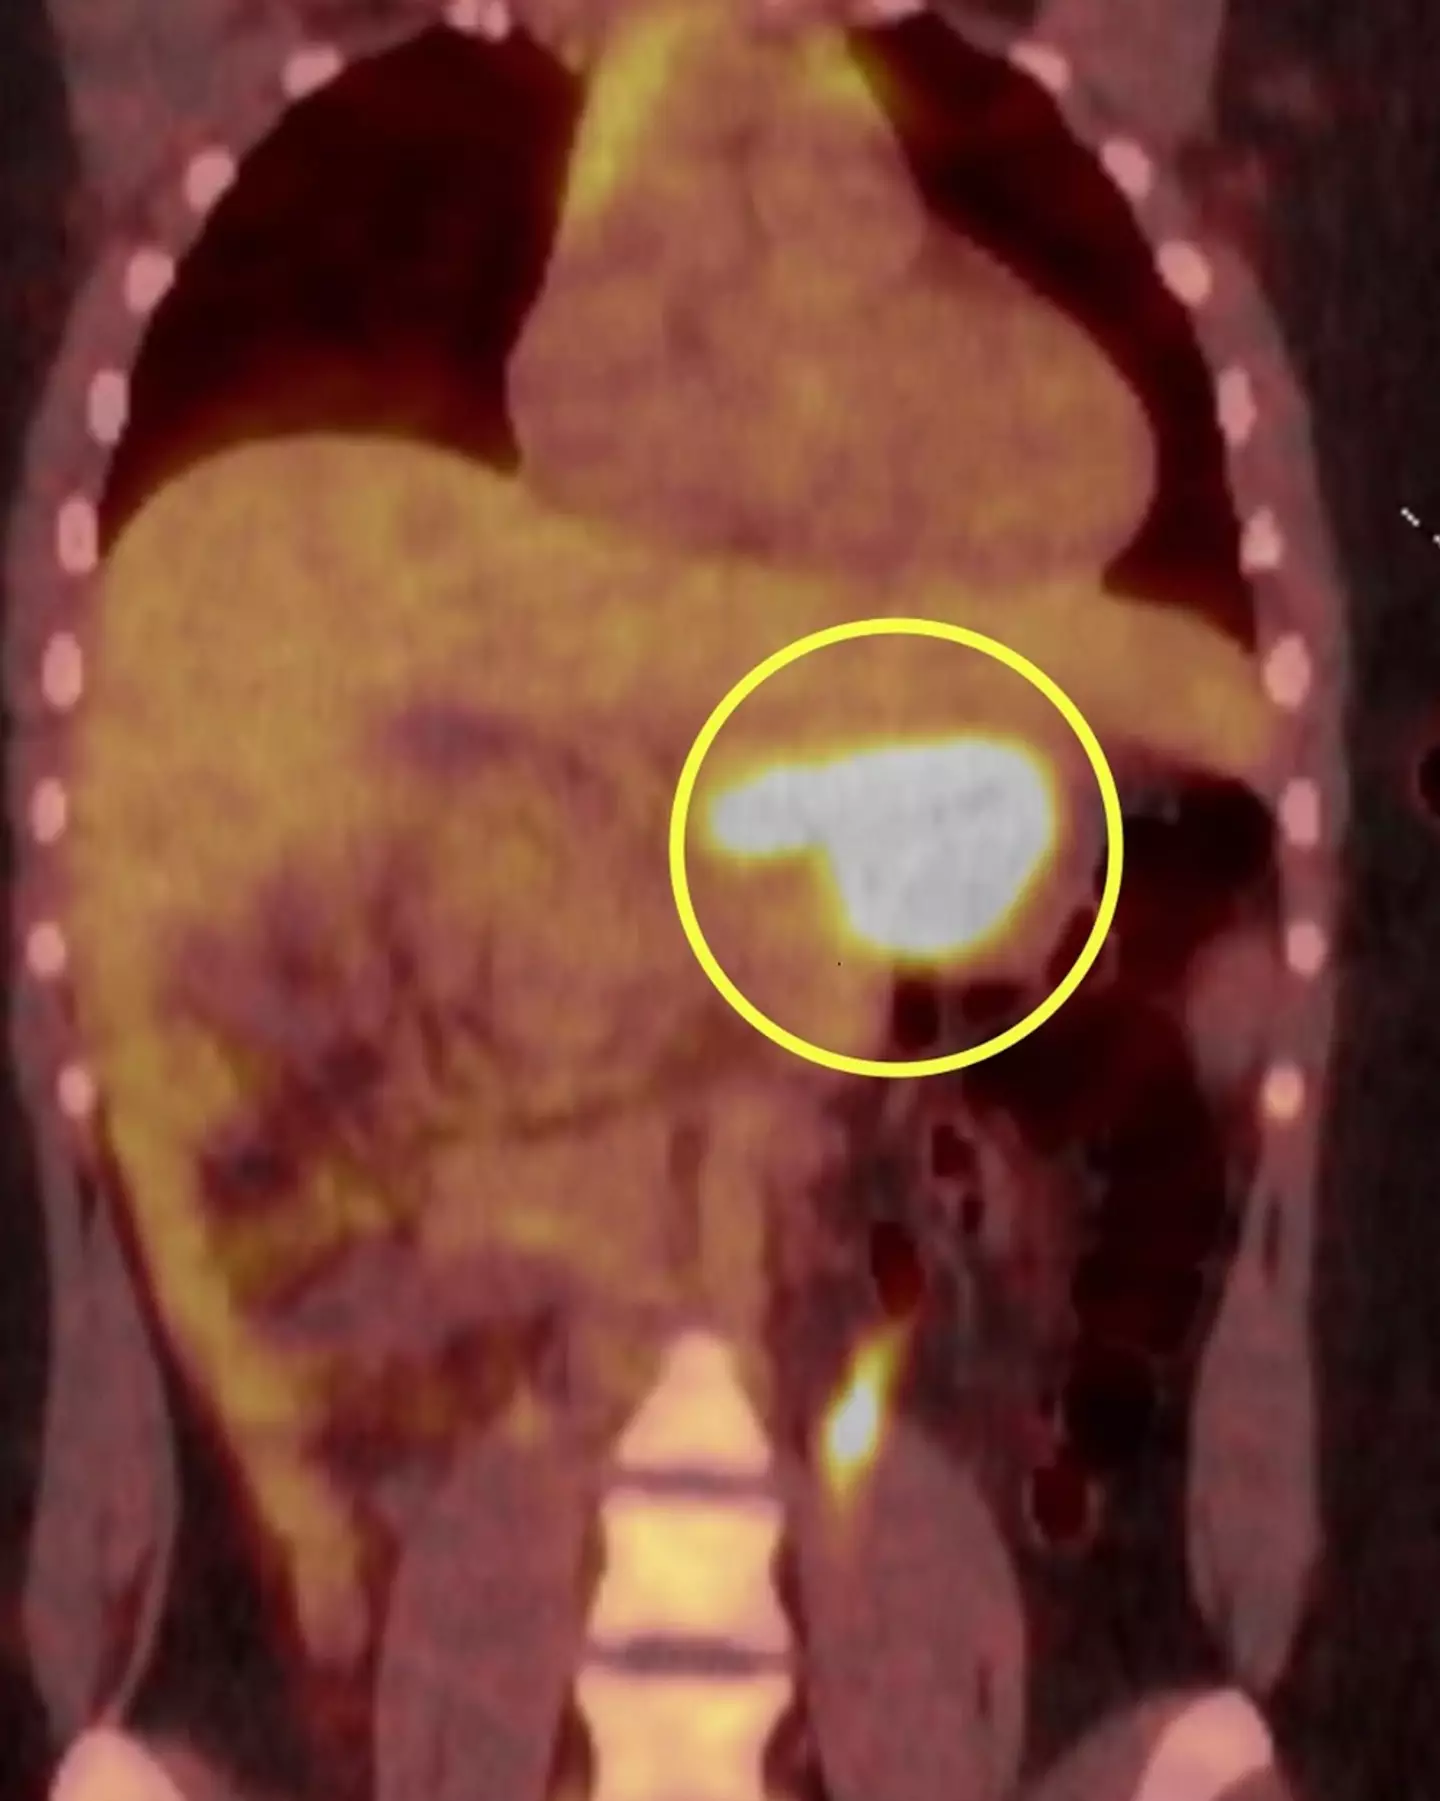

After begging for some sort of investigation, Bayliss underwent a endoscopy that confirmed her worst fears; she had a 6cm tumour in her stomach.

Doctors explained that the specific condition was known as a Gastro-Intestinal Stromal Tumour (GIST), a rare form of cancer caused by a sarcoma coming into fruition inside a person's digestive system.

Despite receiving the all clear, in September of last year, the vicious disease had returned, with scans showing that the cancer had also spread to her liver, where two small tumours sat.